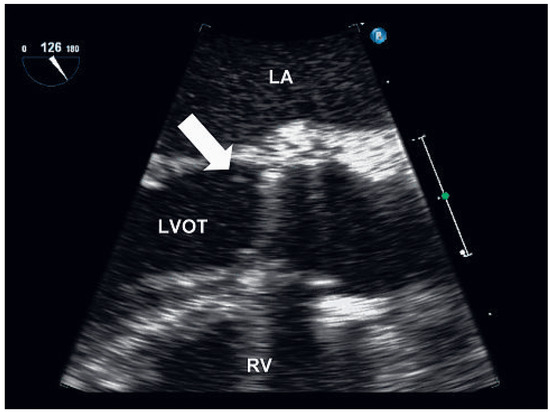

Background: Cardiac resynchronisation therapy (CRT) has become a mainstay in the treatment of patients with severe heart failure mainly due to large clinical trials demonstrating a reduction in morbidity and mortality. The aim of the present study wa...